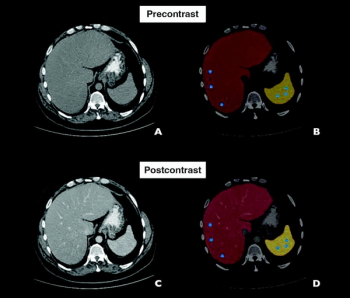

The AI-enabled HealthFLD software demonstrated a 77.8 percent sensitivity rate and a 93.2 percent specificity rate for diagnosing moderate hepatic steatosis on contrast-enhanced CT scans in a recent study of over 2,900 patients.